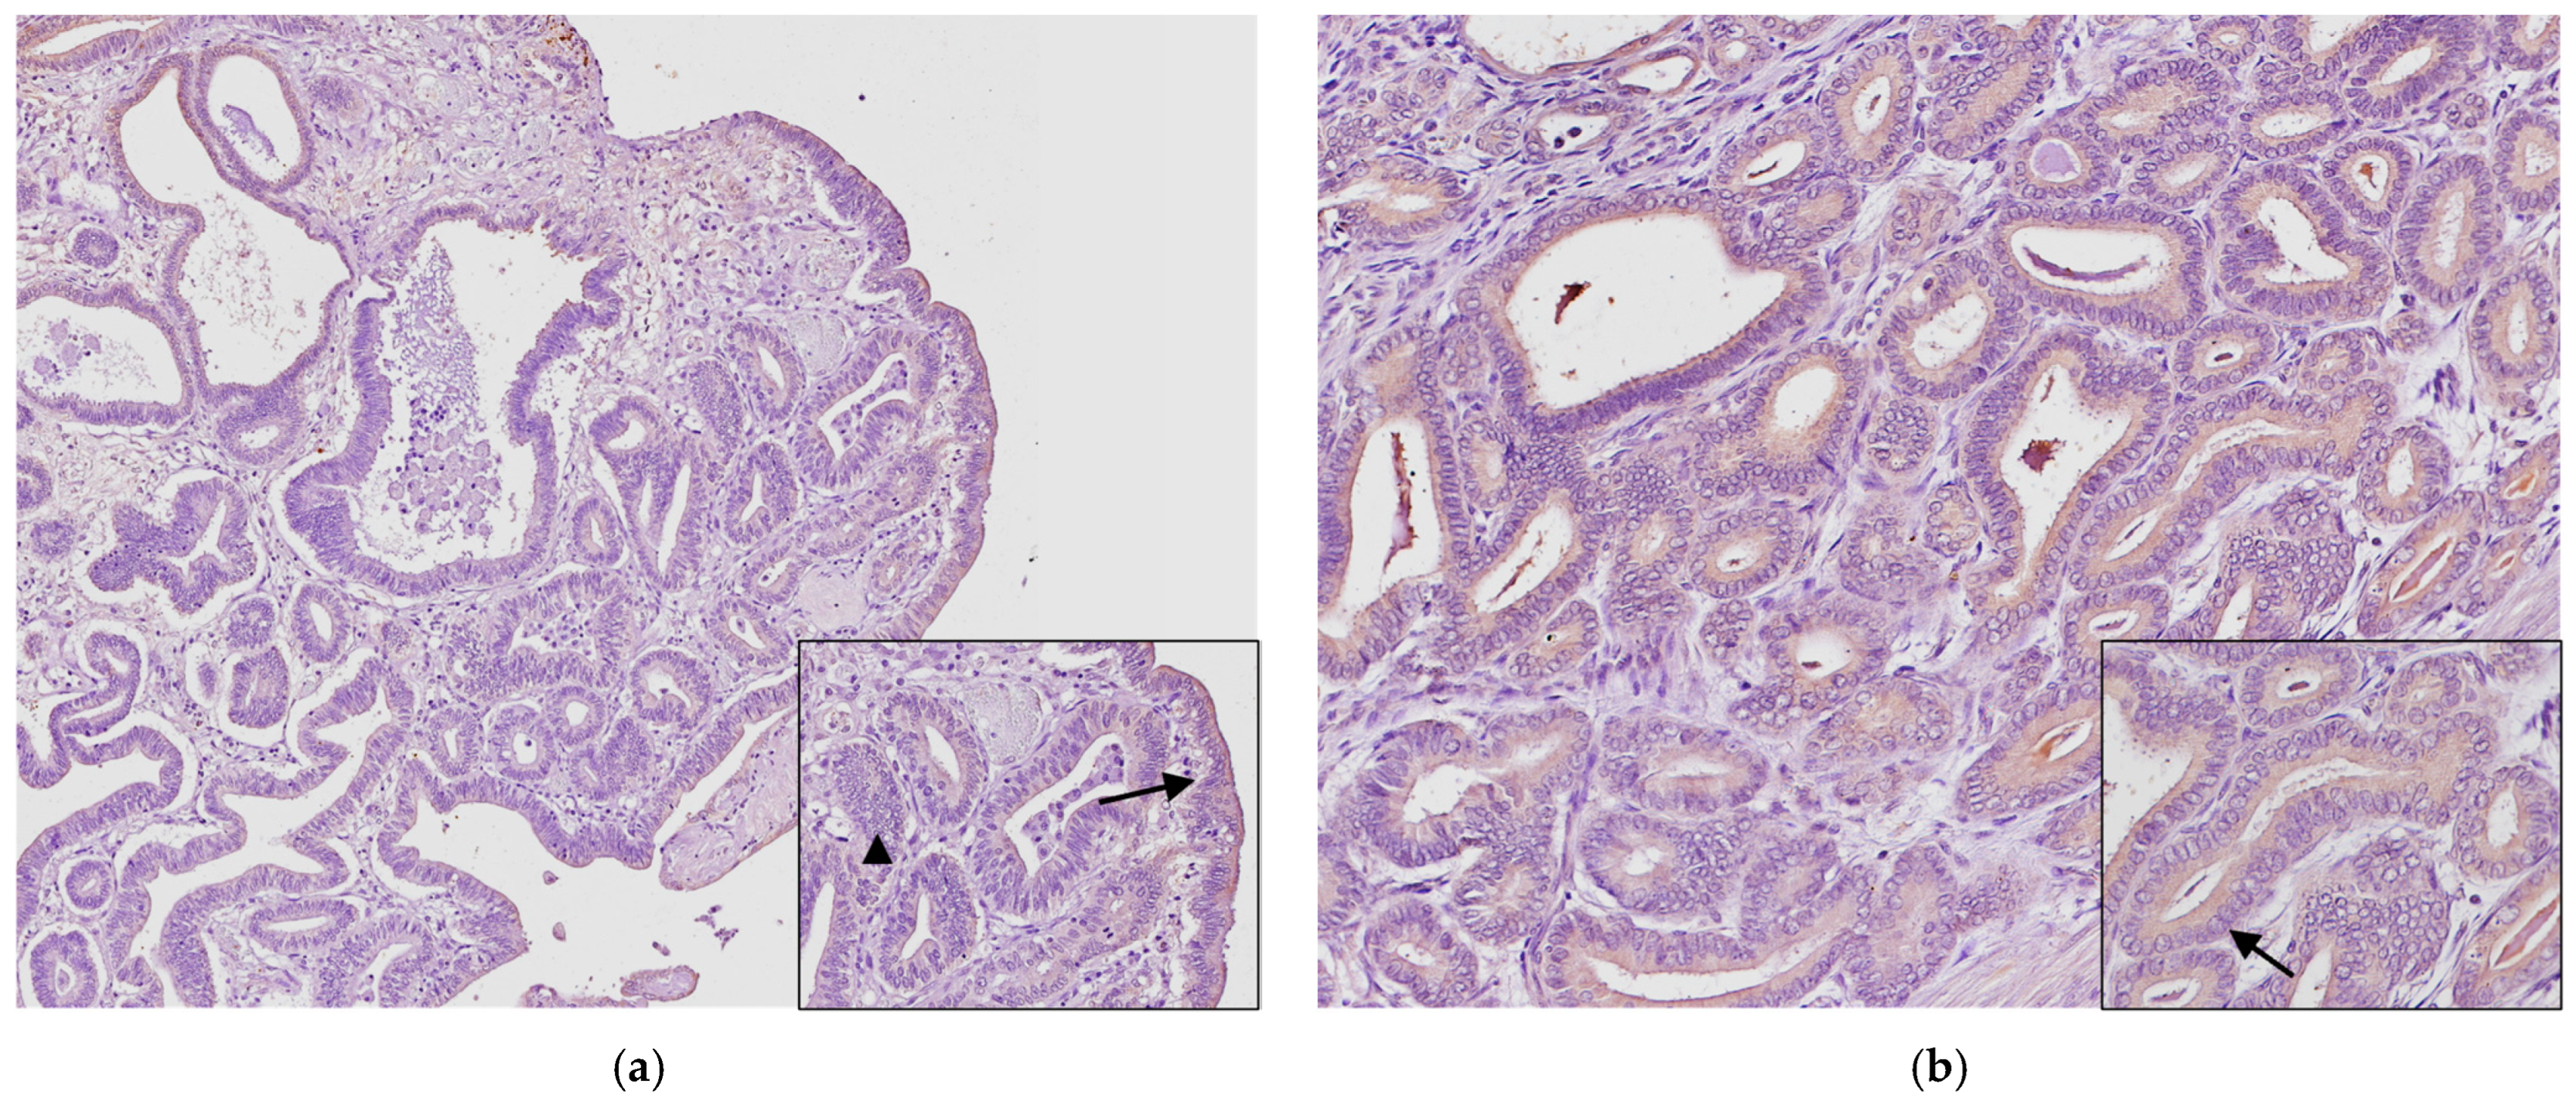

3.3. Immunohistochemistry

3.4. Follow-Up and Therapy